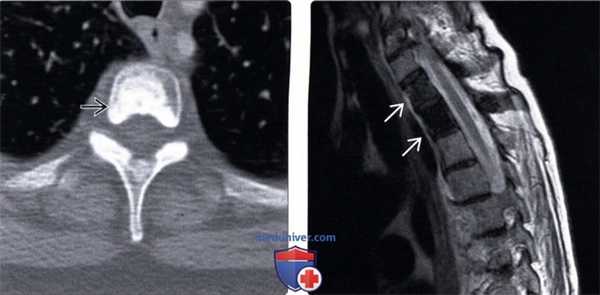

(Слева) Аксиальный КТ-срез: остеобластический метастаз рака молочной железы, занимающий почти целиком тело позвонка.

(Справа) Сагиттальный срез, Т2-ВИ: у этой же пациентки видны остеобластические метастазы в телах двух верхних грудных позвонков. Отмечается снижение интенсивности сигнала, характерное для кортикальной кости и связанное с плотной минерализацией губчатой кости тел позвонков.